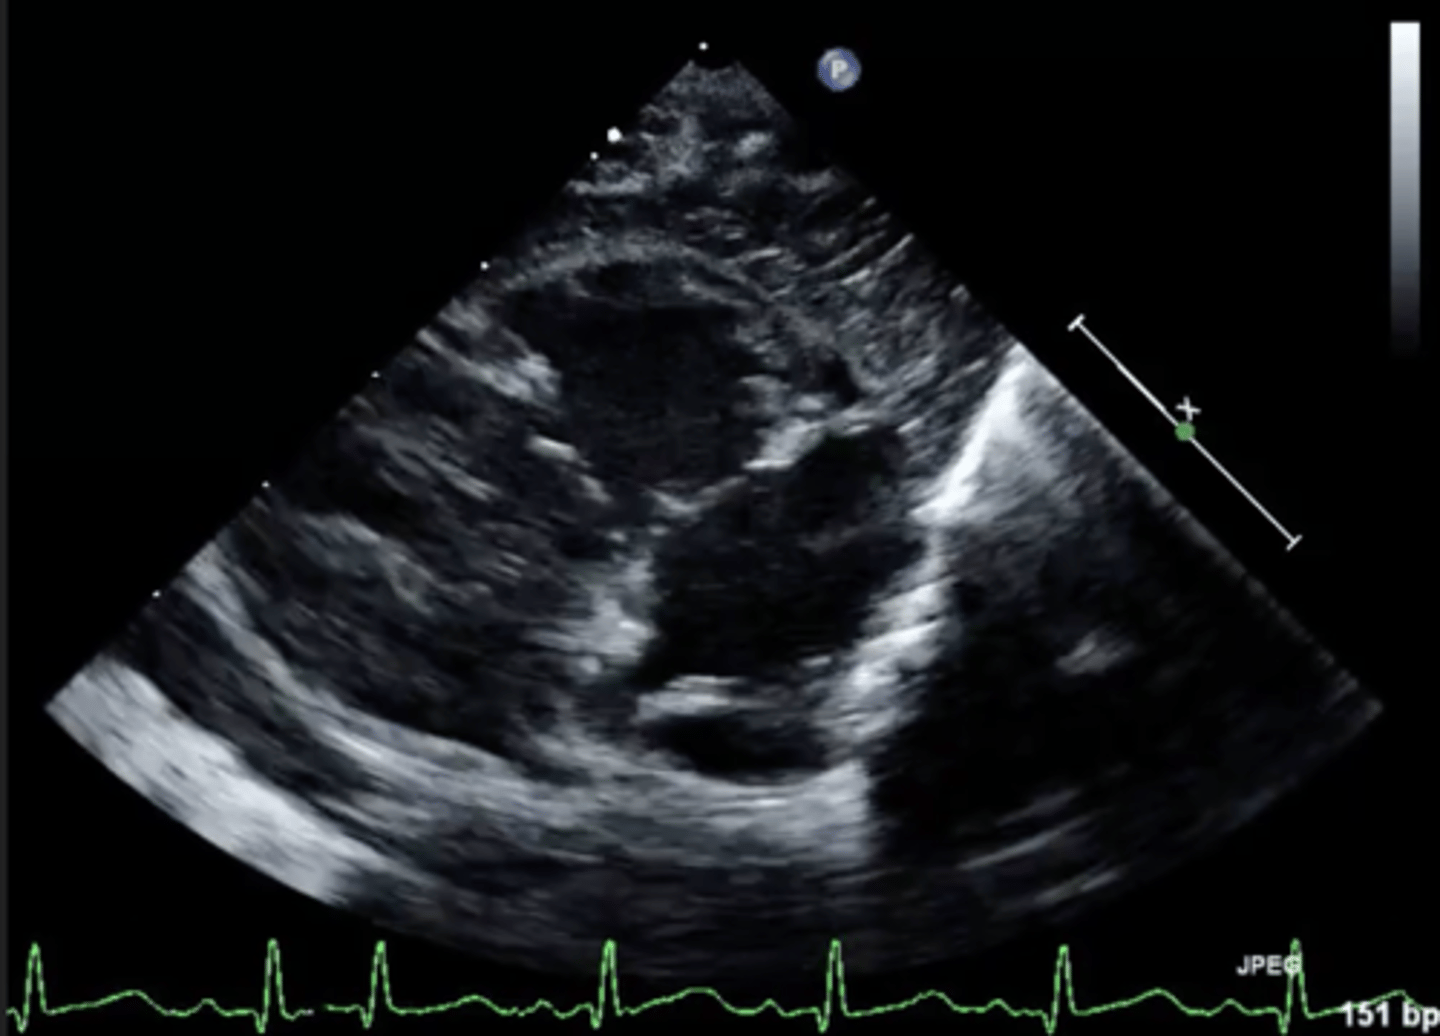

MV PLAX (top leaflet)

AMVL

MV PLAX (bottom leaflet)

PMVL